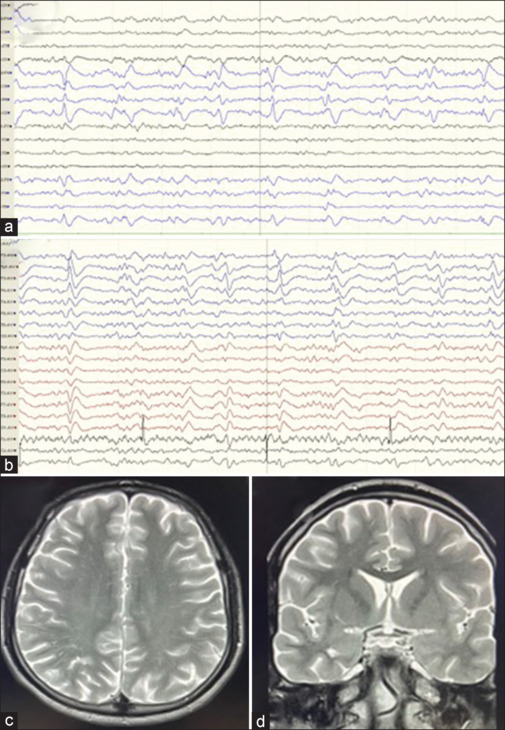

A young male with no known addictions and comorbidities presenting with recurrent clonic-myoclonic movements, initially localized to the left corner of the mouth and left upper limb, evolving into epilepsia partialis continua, despite appropriate sequential antiepileptic medications, subsequently progressed to refractory status epilepticus. He was tested positive for HIV infection and his neuroimaging revealed nonenhancing lesions, a novel finding in HIV-related encephalitis. We managed him with intravenous immunoglobulin along with multiple antiepileptic medications and highly active antiretroviral therapy (ART), and he exhibited a rapid clinical recovery over 3 weeks. This case highlights the importance of initiating immunomodulatory therapy promptly at presentation and underscores the challenges of managing drug interactions between antiepileptic drugs and antiretroviral therapy (ART), emphasizing the need for careful selection of medications in HIV-infected individuals.